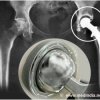

MRI TO 'SEE THROUGH' METAL SCREWS DEVELOPED TO FOLLOW PATIENTS AFTER HIP FRACTURE SURGERY

People who sustain the most common type of hip fracture, known as a femoral neck fracture, are at increased risk of complications. A special type of MRI developed at Hospital for Special Surgery in collaboration with GE Healthcare can show a detailed image following fracture repair, without the distortion caused by metal surgical screws that are problematic in standard MRIs.

With respect to femoral neck hip fractures, this is the first MRI that can "see through" surgical screws to detect early signs of osteonecrosis, so that interventions can be initiated before there is further damage, such as collapse of the bone or osteoarthritis.

In the study, patients had an MRI known as a "multi-acquisition variable-resonance image combination," or MAVRIC MRI, three months and 12 months after surgery. "The MAVRIC MRI provided us with information that could not be ascertained from x-rays or a standard MRI," Dr. Potter explained. "A special 3-D fast spin echo technique minimized distortion caused by metal screws used to repair the fracture, facilitating assessment of the hip joint and any potential problems concerning osteonecrosis or non-union."